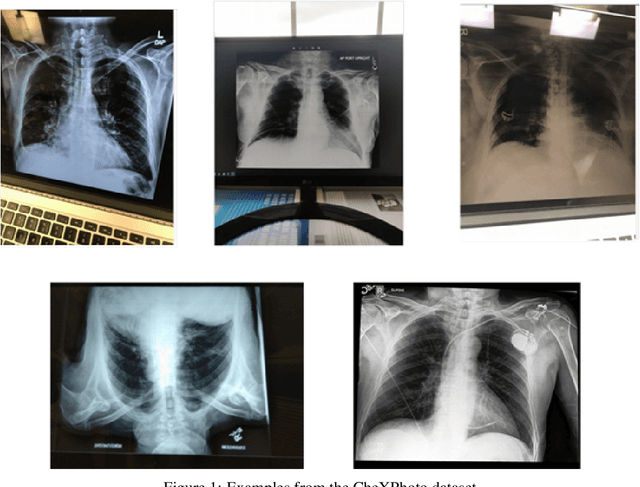

Abstract:Recently, computer-aided diagnostic systems (CADs) that could automatically interpret medical images effectively have been the emerging subject of recent academic attention. For radiographs, several deep learning-based systems or models have been developed to study the multi-label diseases recognition tasks. However, none of them have been trained to work on smartphone-captured chest radiographs. In this study, we proposed a system that comprises a sequence of deep learning-based neural networks trained on the newly released CheXphoto dataset to tackle this issue. The proposed approach achieved promising results of 0.684 in AUC and 0.699 in average F1 score. To the best of our knowledge, this is the first published study that showed to be capable of processing smartphone-captured radiographs.

Abstract:We initially proposed a deep learning approach for foreign objects inpainting in smartphone-camera captured chest radiographs utilizing the cheXphoto dataset. Foreign objects which can significantly affect the quality of a computer-aided diagnostic prediction are captured under various settings. In this paper, we used multi-method to tackle both removal and inpainting chest radiographs. Firstly, an object detection model is trained to separate the foreign objects from the given image. Subsequently, the binary mask of each object is extracted utilizing a segmentation model. Each pair of the binary mask and the extracted object are then used for inpainting purposes. Finally, the in-painted regions are now merged back to the original image, resulting in a clean and non-foreign-object-existing output. To conclude, we achieved state-of-the-art accuracy. The experimental results showed a new approach to the possible applications of this method for chest X-ray images detection.